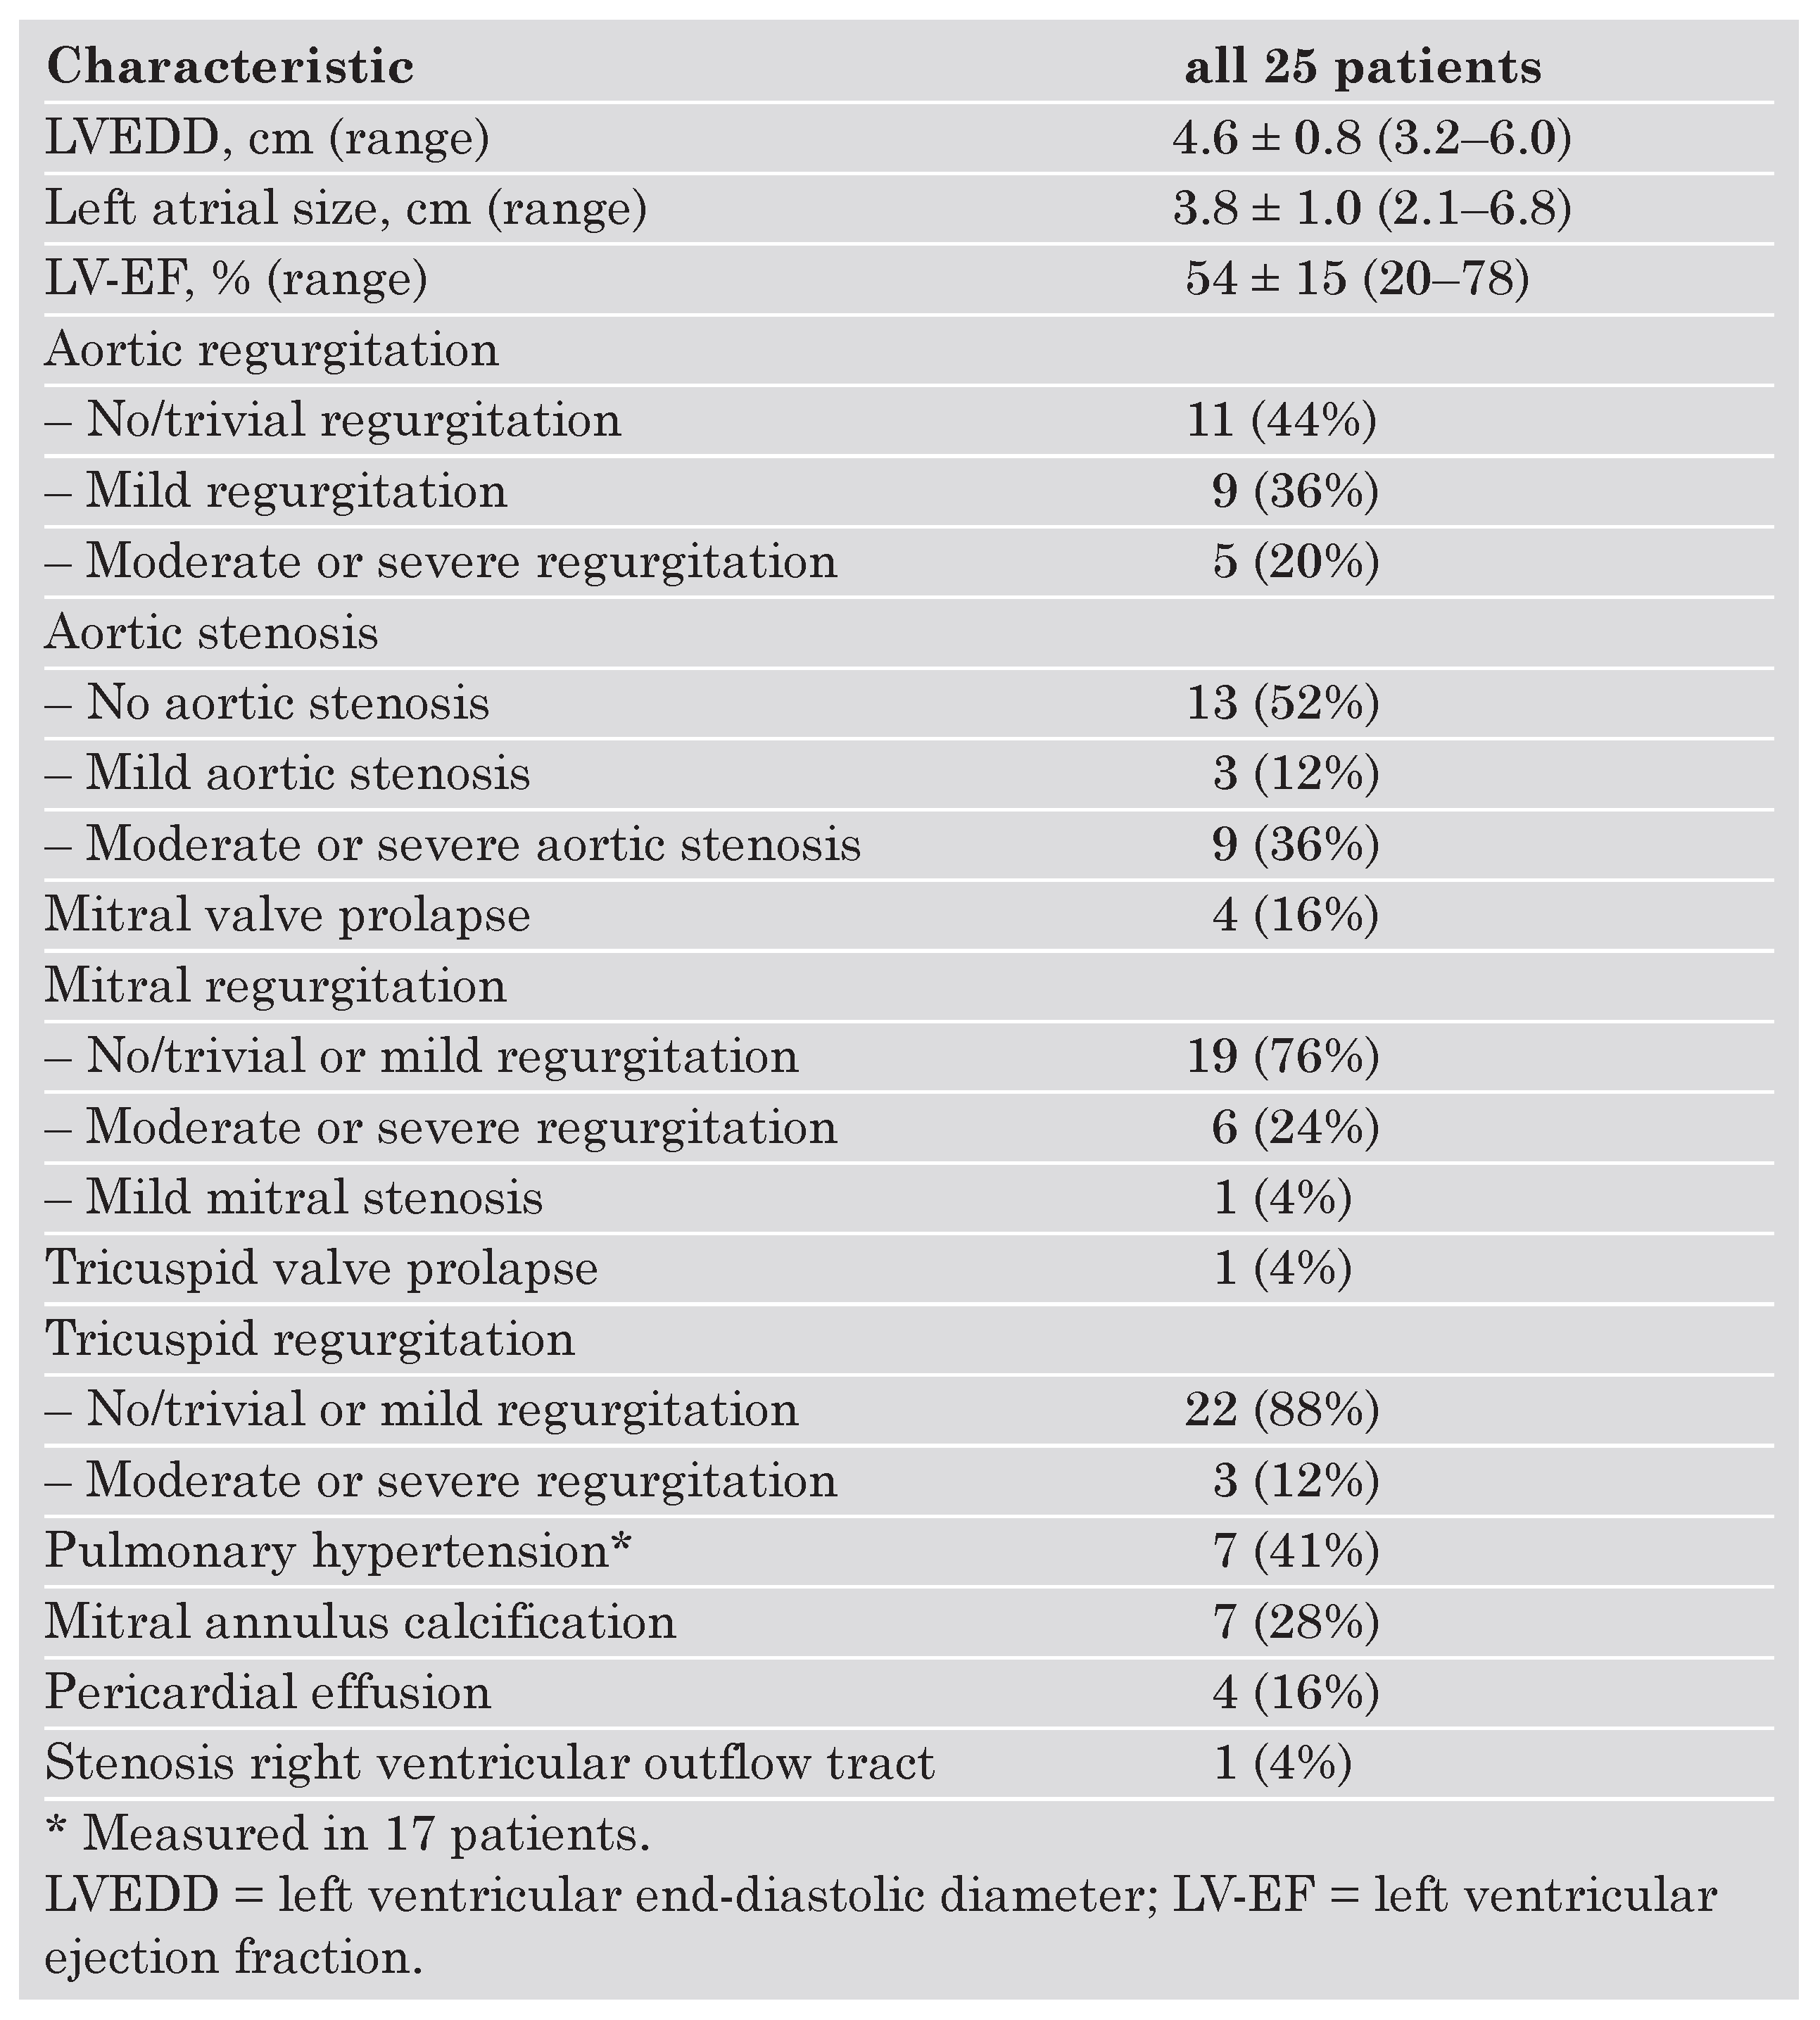

Echocardiographic findings

|